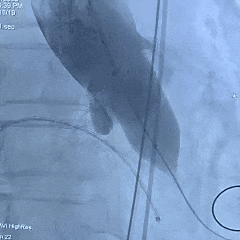

手术过程

左冠造影检查

20mm球囊扩张,无腰无漏,球囊轻微滑动

TF23瓣膜0位初始释放

瓣膜第一次展开造影评估,位置偏浅,回收调整

第二次释放造影评估

瓣膜深度可,展开良好,无瓣周漏

瓣膜解锁后造影评估

瓣膜深度合适形态良好,冠脉灌注良好,无瓣周漏

最终多角度观察瓣膜形态,瓣膜展开良好

超声测量流速1.5m/s,手术结束